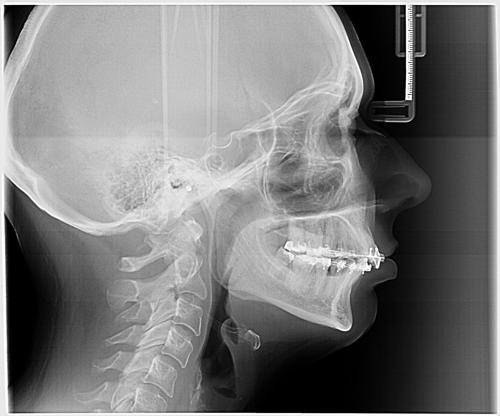

https://www.petmd.com/dog/conditions/mouth/c_dg_upper_lower_jaw_fracture

Aug 16, 2022 - The maxilla forms the upper jaw (Maxilla) and holds the upper teeth in place; whereas, the mandible, also called the jawbone, forms the lower jaw and holds the...

https://emergeortho.com/conditions/spine-and-neck-fractures/

Jul 9, 2020 - Neck fractures can be caused by osteoperosis or pathologic tumors and blood vessel expansion putting your spinal column at significant risk for fracture.

https://www.briskmanandbriskman.com/practice-areas/chicago-car-accident-lawyer/facial-fractures/

Jul 9, 2025 - Car accidents can change your life in an instant. One of the most shocking and painful injuries someone can experience after a collision is a facial fracture.